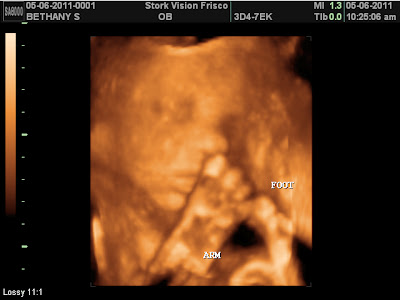

This is the second time we've got a cool foot picture. The tech said her foot is right up against me and anytime I am feeling kicks on the right side it is definitely her feet. (That after I told her what the mean ultrasound lady at my doctor's office said.) I'm wondering if we will ever get to make out that it's a foot from the outside. I think the way she has it now, it could be a possibility.

Her foot is up near her face too. She is literally folded in half.